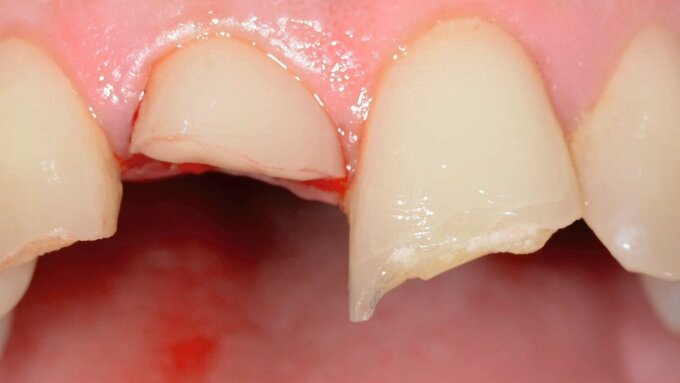

Aufgrund einer erwartungsgemäß erschwerten fotografischen Dokumentation bei der zahnärztlichen Behandlung in der mobilen Zahnmedizin wird die klinische Falldokumentation an einer Seniorin vorgenommen, deren Therapiefähigkeit und Eigenverantwortlichkeit nicht eingeschränkt war. Die 76-jährige Patientin stellt sich zur routinemäßigen Kontrolle in der Poliklinik für Zahnerhaltungskunde vor. Die allgemeine Anamnese ergab Zustand nach Meningeom, eine Quecksilber- und eine Birkenpollenallergie und einen erhöhten Blutdruck, der mit Lercanidipin eingestellt war. Am circa 20 Jahre alten Gussmetall-Inlay an Zahn 24 wurde dabei ein sondierbarer Randspalt festgestellt (Abbildungen 2a und 2b).

Nach Reinigung der Zähne und Bestimmung der Zahnfarbe wurde Kofferdam zur absoluten Trockenlegung angelegt. Mit rotierenden Instrumenten wurde ein Teil des Gussmetall-Inlays im sondierbaren Bereich entfernt und die Karies exkaviert (Abbildungen 2c und 2d). Anschließend wurden alle zu reparierenden Oberflächen (Gussmetall, Dentin und Schmelz) mit reinem Aluminiumoxid, Partikelgröße 50 µm (Rondoflex®/KaVo), unter Verwendung von Wasser abgestrahlt und danach gründlich mit Wasser abgespült (Abbildungen 2e und 2f). Die selektive Schmelzätzung erfolgte mit 37,5-prozentiger Phosphorsäure (Email Preparator®/Ultradent) für 30 Sekunden (Abbildung 2g). Nach Abspülen der Phosphorsäure mit Wasser wurde ein Universaladhäsiv (Clearfil Universal Bond Quick® / Kuraray Noritake) aufgetragen (Abbildung 2h, Glanz soll erhalten bleiben, Verdunstung einige Sekunden abwarten) und dann lichtpolymerisiert.

Im Anschluss wurde die Reparaturrestauration mit Komposit (Ceram X Spectra®/Dentsply Sirona) eingebracht (Abbildung 2i). Im Sinne des Restaurationsunterhalts wurden bei der Politur die Restaurationsränder der Gussmetall-Inlays an den Zähnen 24 und 25 finiert und zusammen mit der Kompositrestauration hochglanzpoliert (Abbildungen 2j und 2k).